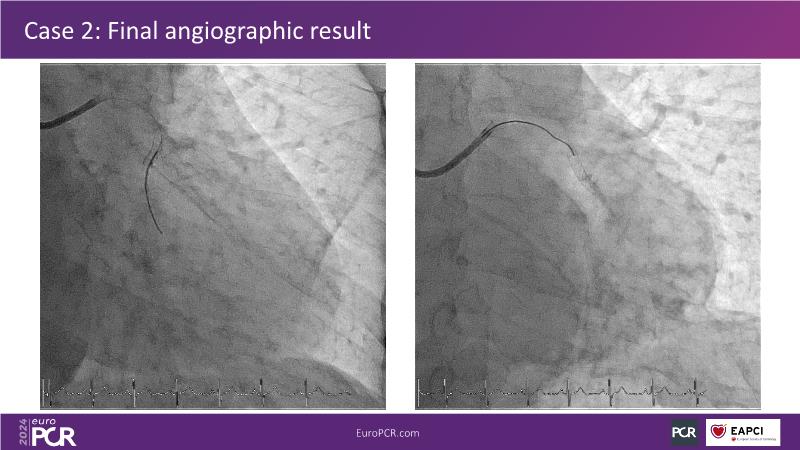

PCI in patients with diabetes: next generation DES + DCB stent platform in action

Watch this session on PCI in diabetic patients to learn about a groundbreaking technology addressing the complexities of this critical subgroup. Discover the next-generation DES and DCB stent platform and the innovative Envisolution technology behind it. Understand how it works, its advantages in managing complex cases, and what sets it apart from other technologies. Gain insights into the future of polymer-free DES + DCB stent technology and its potential impact on patient care.